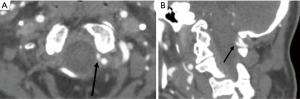

All the images were reviewed in consensus by three radiologists, each of whom had at least ten years of experience in CT diagnosis. By consulting the three-section classification criteria of V3 (13,28), we divided V3 into three subsegments: vertical portion originating from the foramen of C2, horizontal portion originating from the foramen of C1, and extradural portion originating from the posterior atlantooccipital membrane and ending at the site of piercing the dura. The three subsegments were referred to as V3v, V3h, and V3e, respectively (Figures 1-4). The number of branches was recorded. With regard to the arrangement of the branch of V3, the number 0 indicated no branches in the subsegment, and the number 1 indicated no less than one branch in the subsegment (Figure 1). There were eight kinds of arrangements of the branches altogether (000; 100; 110; 111; 010; 011; 001; 101). After an agreement was reached by consensus, all the data were confirmed. The reproducibility was assessed by comparing a subset of measurements made on 100 randomly selected cases. The radiologists were blinded to the measurements taken by the other radiologists. The 100 cases were reviewed by three observers, and interobserver agreement was calculated. All the data were imported into R statistical software, version 3.6.1, to be processed further.

The vertebral artery has a tortuous shape to meet the need for flexible movement and to facilitate smooth blood flow. V3 is anatomically defined as the vertebral artery that passes from the foramen of C1 to the site of the piercing dura, and it is radiologically defined as the artery passing from the foramen of C2 to the piercing site (26,27). Considering the occipito-atlantoaxial complex is a functional complex, we adopted the latter definition. The V3 that was identified was then divided into two portions demarcated by the foramen of the C1 process, namely, the horizontal and vertical portions, as reported in previous studies. In this study, we divided V3 into three subsegments, namely, the V3v, V3h, and V3e subsegments (13,29). V3e was the section passing from the posterior atlantooccipital membrane to the site of piercing the dura (28). The V3v was easily identified on CTA images. The starting point of V3e was defined as the point of intersection of the course of V3 and the superior border of C1 to which the posterior atlantooccipital membrane attached (29). The terminal point of V3e was marked by the density difference between the cerebrospinal fluid and dura mater on CTA images. The branch arising from V3h was defined as the suboccipital artery of Salmon that supplied the neighboring muscles. The frequency of the artery of Salmon was 20% in a study of 10 cadavers and 67% a study of 15 cadavers (26,27). The frequency of the artery of Salmon was 17.07–20.21% in V3h. Our results are consistent with those reported by Tubbs RS et al. Three branches arising from the V3h were discovered by dissecting cadavers (27), while no more than 2 branches were revealed in our research. The frequency of the branch was 25% in V3v and less than 6% in V3e. The rate of asymmetry in the arrangements of the branches of V3 was 30% according to the autopsy; in other words, the rate of symmetry was 70% in the arrangements (27). In our study, all eight arrangements of branches of V3 were symmetric, regardless of the sex and side of the patient. The permutation of (0,0,0) was the most frequently occurring permutation, followed by (1,0,0), and (0,1,1) was the least frequent (Table 3).

It was essential for a surgeon to acquaint every patient’s bifurcations of V3 on CTA before the operation. V3e is fixed by surrounding structures, and its branch has important clinical significance when an operation is conducted in the cranio-occipital region because it might cause mortal bleeding (28-30). The branch of V3 was often ignored on the CTA images by volume rendering process in postprocessing. It cannot be stressed enough that a surgeon must determine the number and locations of the branches of V3, and it is helpful for surgeons to conduct surgical planning to minimize the volume of bleeding.